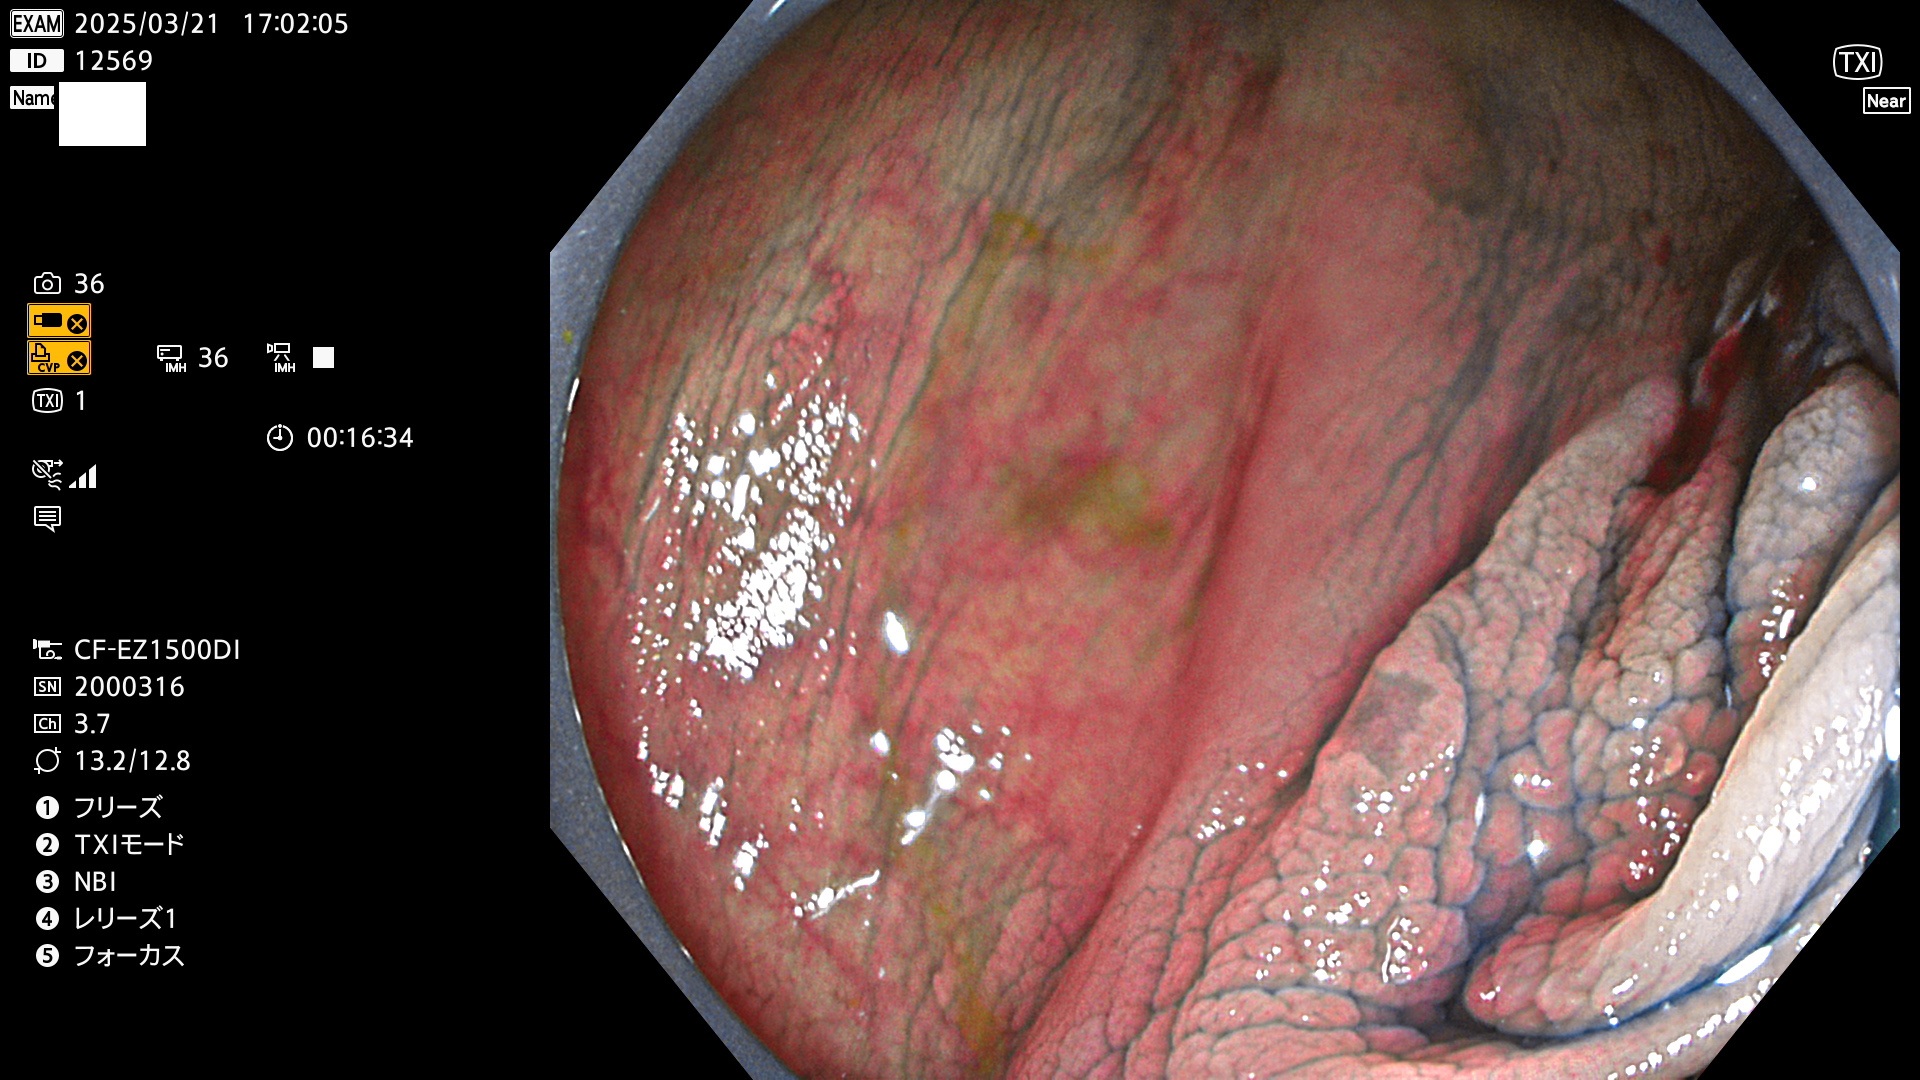

今週のUb、Uc型腺腫

完全に平坦な物をUb、陥凹している物をUcと呼びます。Ubは認識が困難で、Ucはびらん(炎症)と紛らわしいために見落とされやすく、「内視鏡後・大腸癌」の原因になります。

抽出の対象期間 2025年3月20日〜3月23日の4日間(48件の検査)10個 (10/48=21%)